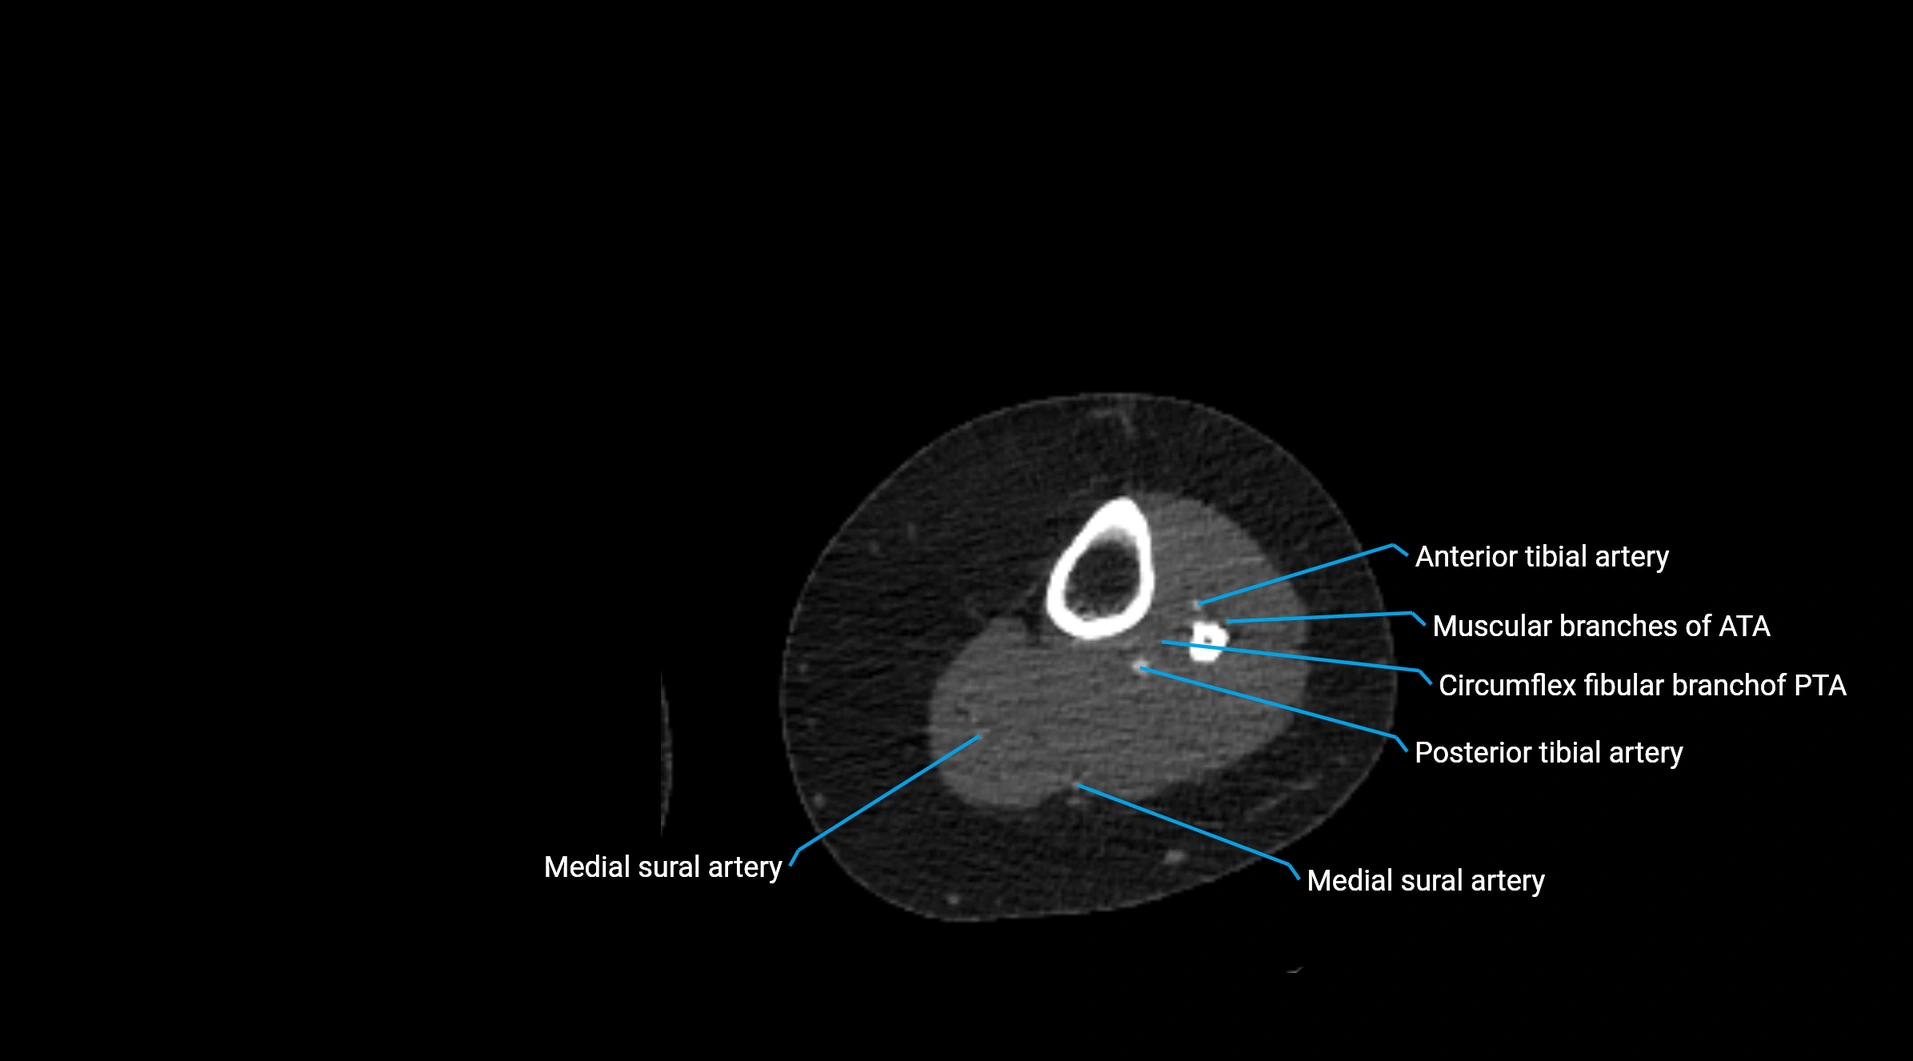

Contrast-enhanced CT (CTA):

• Gold standard for abdominal aortic imaging

• Provides excellent detail of lumen, wall, aneurysm, thrombus, and branch vessels

• Multiplanar and 3D reconstructions help in aneurysm measurement, stent graft planning, and dissection evaluation